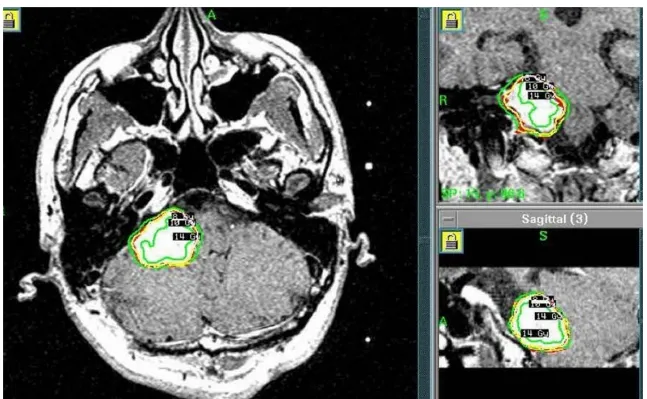

2004年5月,患者确诊为听神经瘤并接受首次开颅手术。术后病理检查确认诊断,初期治疗显示右侧桥小脑角区肿瘤呈现不均匀强化表现。为控制术后残留病灶,2005年8月实施伽玛刀治疗。2007年5月随访发现肿瘤再次进展,遂行第二次开颅手术。

2004年4月初始MRI显示右侧桥小脑角区肿瘤不均匀强化。2005年8月首次术后、伽玛刀治疗前影像资料记录肿瘤状态。2007年5月第二次术前MRI评估显示肿瘤进展,术后一个月影像确认切除范围。

定期随访影像资料(图1 E-J)完整记录2008-2013年肿瘤变化情况。2013年末至2014年初复查显示肿瘤再次生长,2014年4月术前MRI显示肿瘤不均匀强化伴脑干受压。术后两个月随访影像确认次全切除结果。